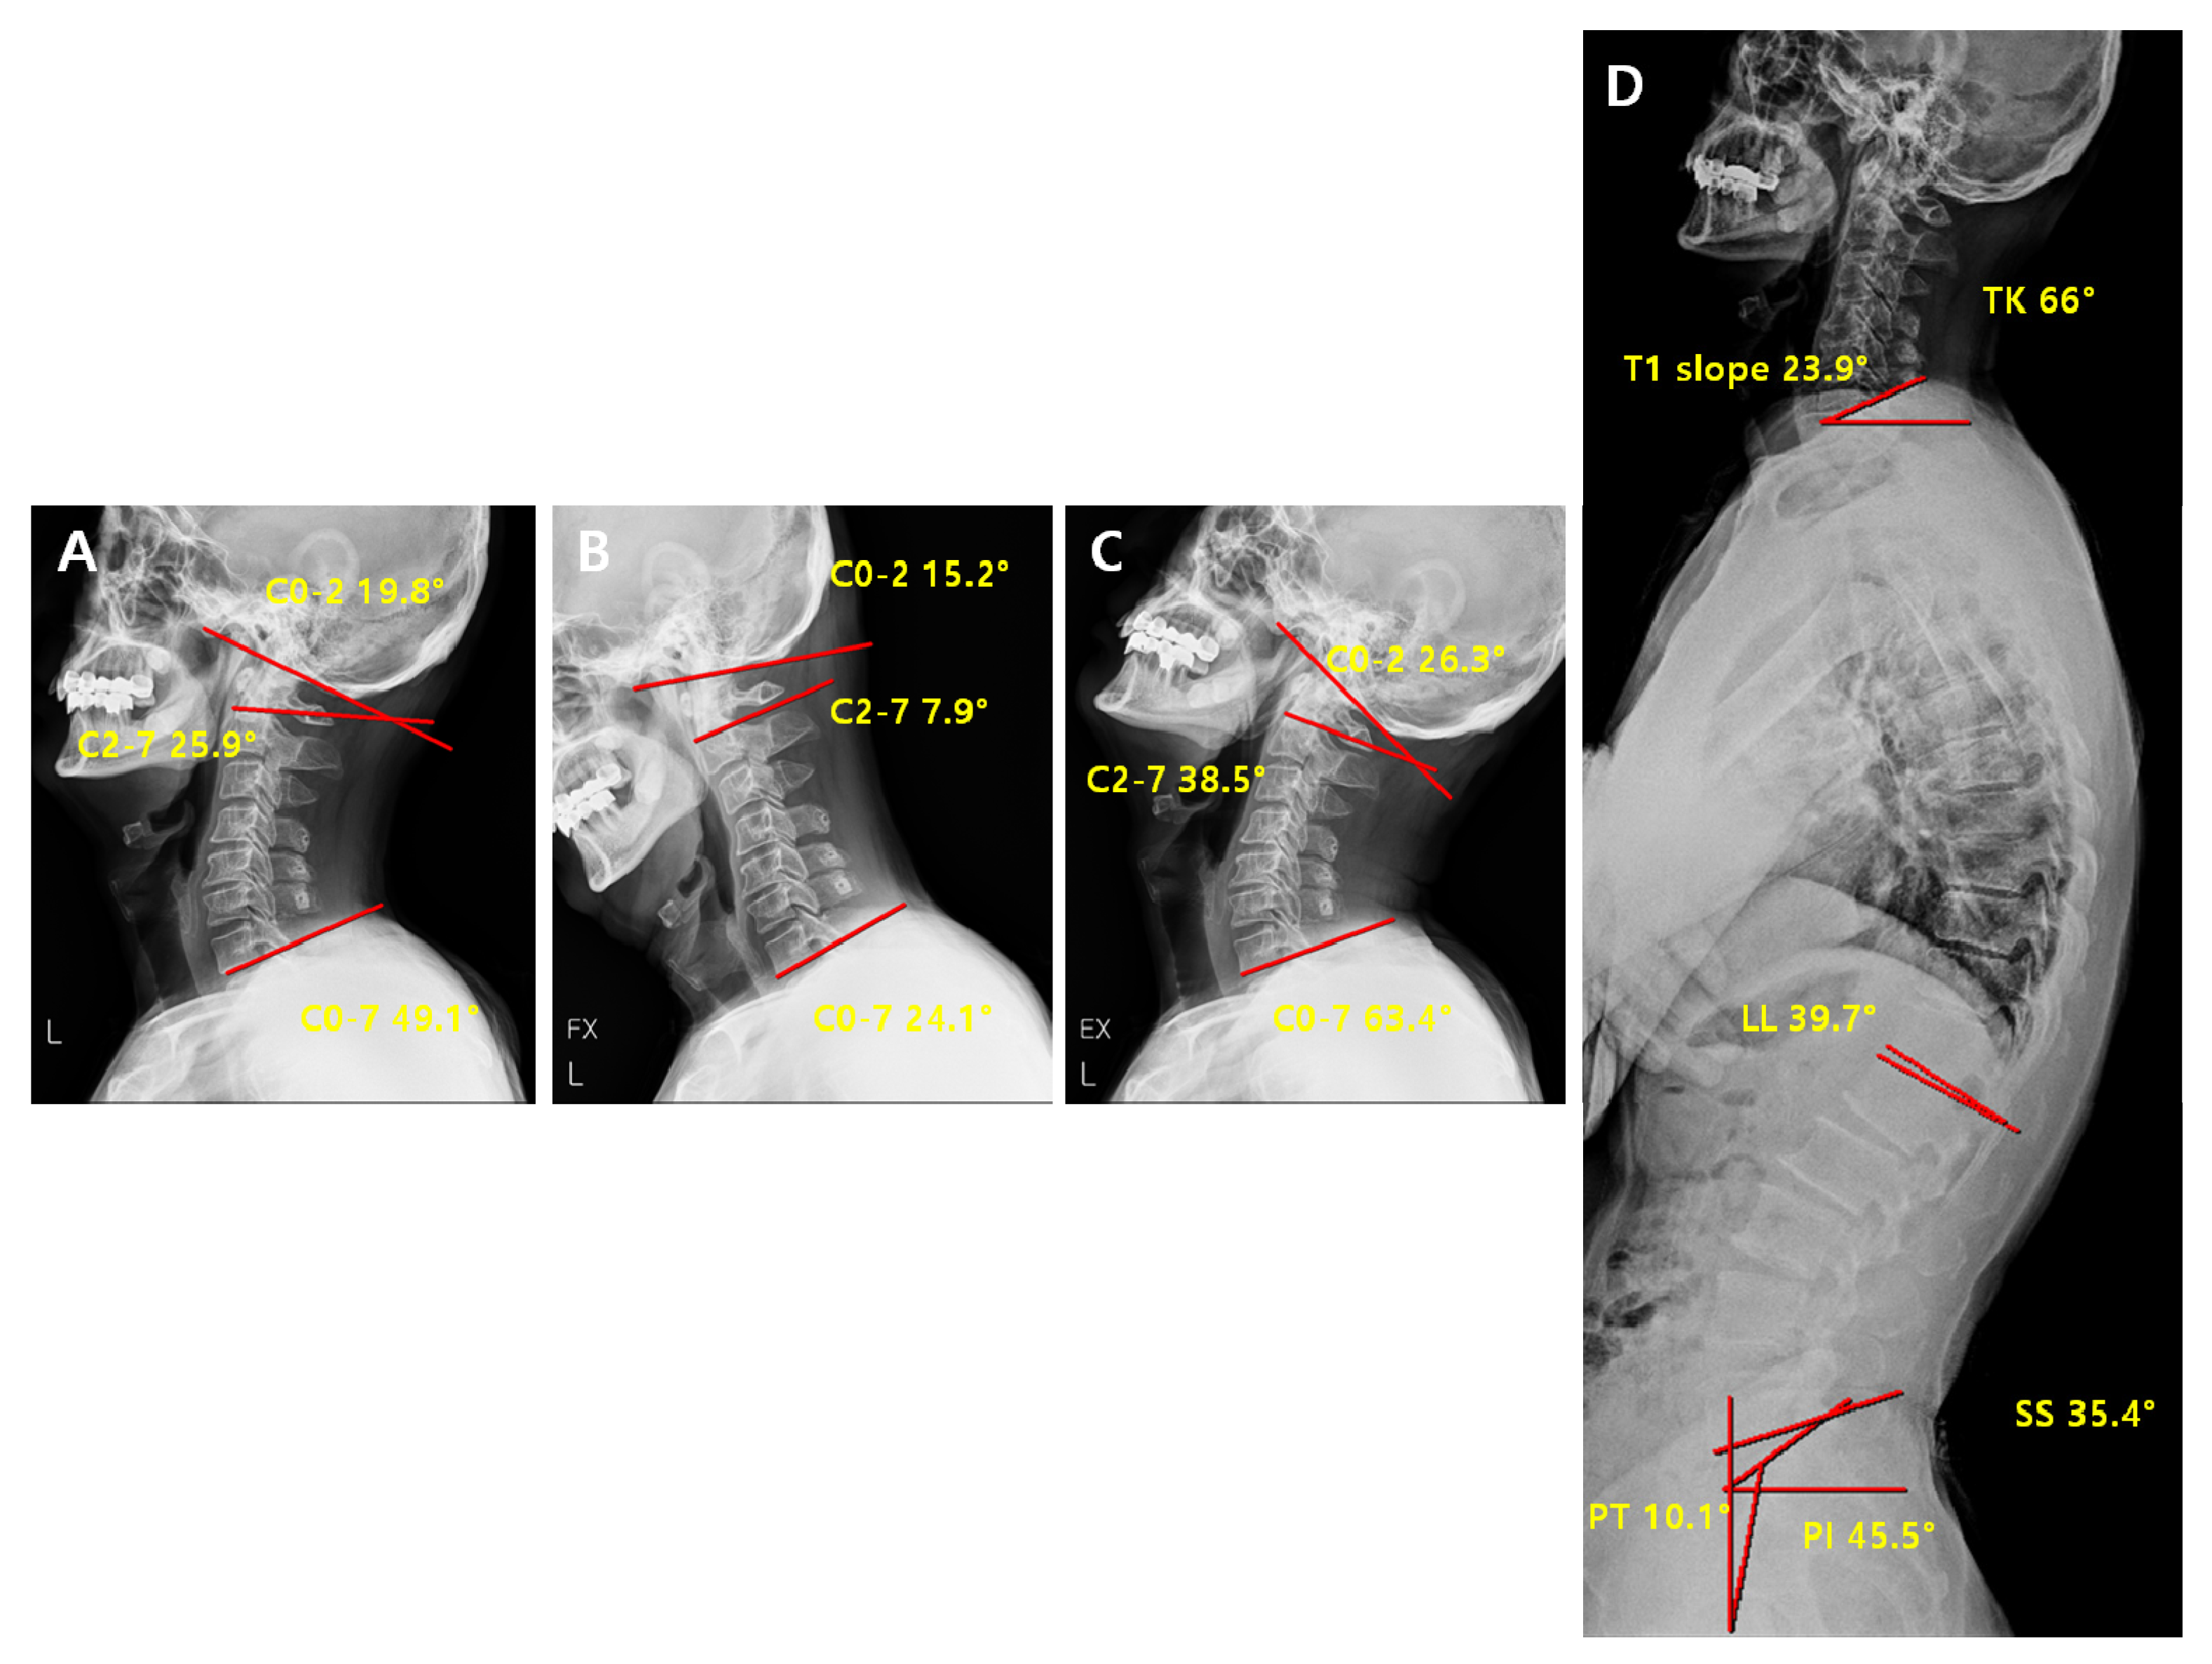

2.3. Radiographic Measurement

2.4. Radiological Analysis